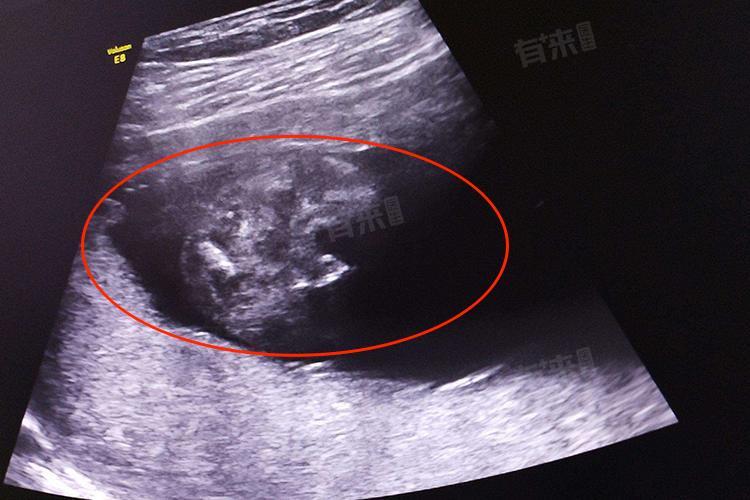

2、超声检查:通过观察胎儿的双顶径、股骨长、头围、腹围等指标,可以了解胎儿的生长发育情况,判断是否存在发育迟缓或异常。